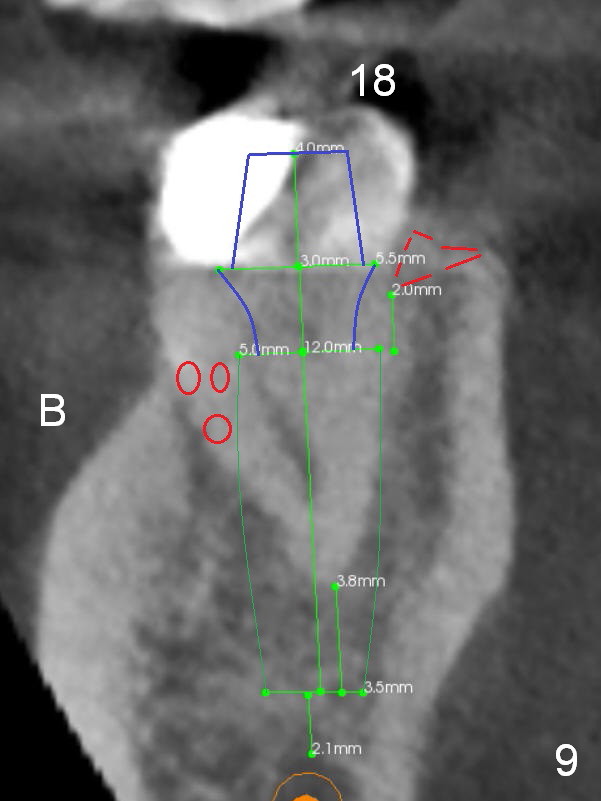

A 35-year-old lady (YL) has periodic nocturnal pain of the lower left quadrant. There is open buccal margin at the abutment of #18 (Fig.1 (from panoramus)). When the pontic and the retainer are removed (Fig.2), there is a large buccal subgingival carious lesion at the tooth #18. The latter has 2 roots, although close to each other. If the extraction turns out to be difficult, section the tooth (Fig.3 red line (no antibiotic)). To avoid contacting the tooth #17, place an implant at the mesial socket of #18 (Fig.5,7). Although it appears that the tooth #20 has no periapical radiolucency (Fig.6,7), the crown will be removed for diagnosis. A 3-unit provisional will be fabricated after an implant is placed at #19 (Fig.7,8) in the same appointment.